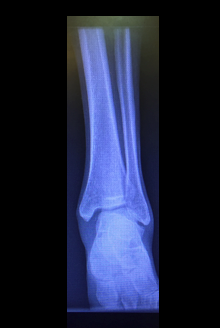

X-ray showed widening of the medial tibiotalar joint space (Image A) and a comminuted fracture of the proximal fibula (Image B). These findings are suggestive of a Maisonneuve fracture with syndesmotic ligament disruption. He was placed in a splint and referred to orthopedic surgery. Ten days later, he underwent operative fixation of his syndesmotic ligament injury.

Image A: Anteroposterior view L ankle